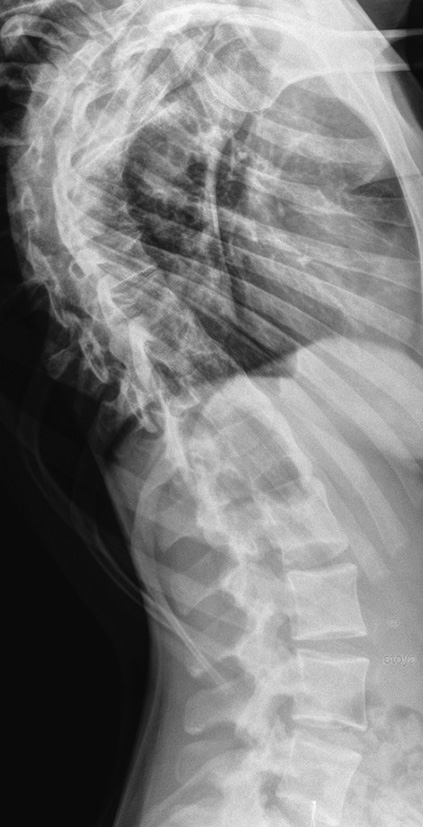

Radiographs, multispiral computed tomography (MSCT) of the spine revealed radiation pattern of severe idiopathic scoliosis of the thoracic spine. The left-sided scoliotic arch Th6–Th12 of 75° according to Cobb was determined. In functional images, the scoliotic arch was rigid, corrected to a value of 70° according to Cobb. The frontal balance was physiological. Rotation and torsion of the vertebrae have secondary degenerative and dystrophic changes in the vertebral-motor segments of the thoracic and lumbar regions (most pronounced at the apices of the scoliotic arches). No areas of bone density were revealed in the spinal canal (Fig. 1, 2).

Fig. 1. X-ray of the spine in a frontal view in a standing position

Fig. 2. X-ray of the spine in a lateral view in a standing position